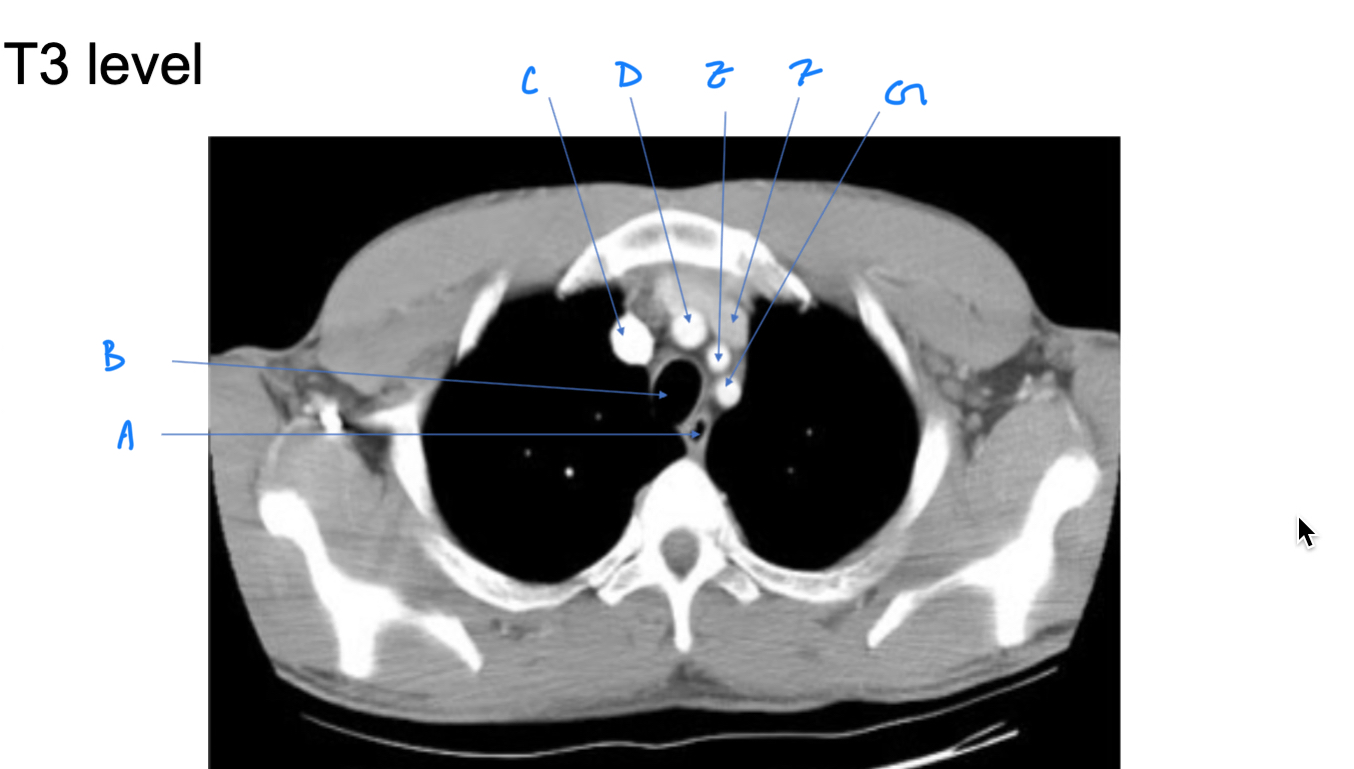

Esophagus

A. Identify

Trachea

B. Identify

R Brachiocephalic v.

C. Identify

Brachiocephalic trunk

D. Identify

L CCA

E. Identify

L Brachiocephalic v.

F. Identify

L Subclavian a.

G. Identify